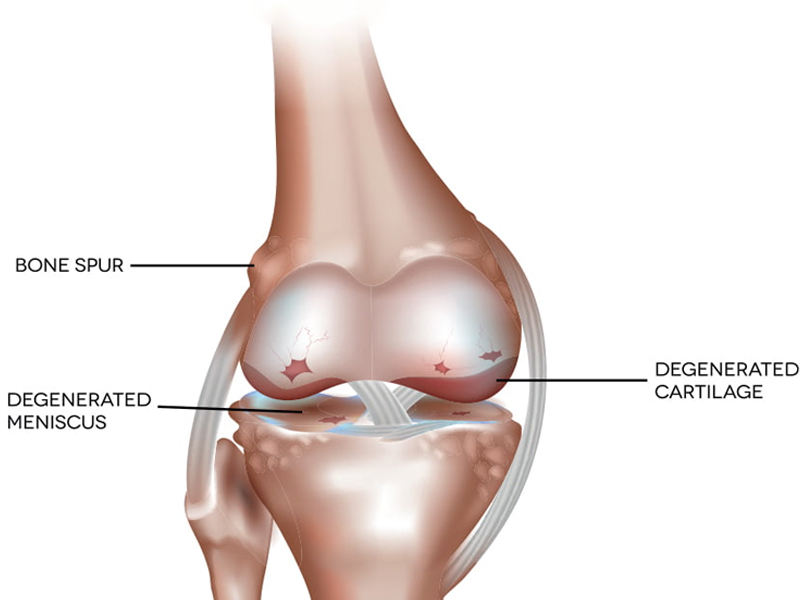

Knee Replacement

Knee replacement surgery replaces parts of injured or worn-out knee joints. The surgery can help ease pain and make...

Knee Arthroscopy

Knee arthroscopy is a surgical procedure that allows doctors to view the knee joint without making...

Cartilage preservation procedures

Articular cartilage is the smooth, white tissue that covers the ends of bones where they come together to form ...